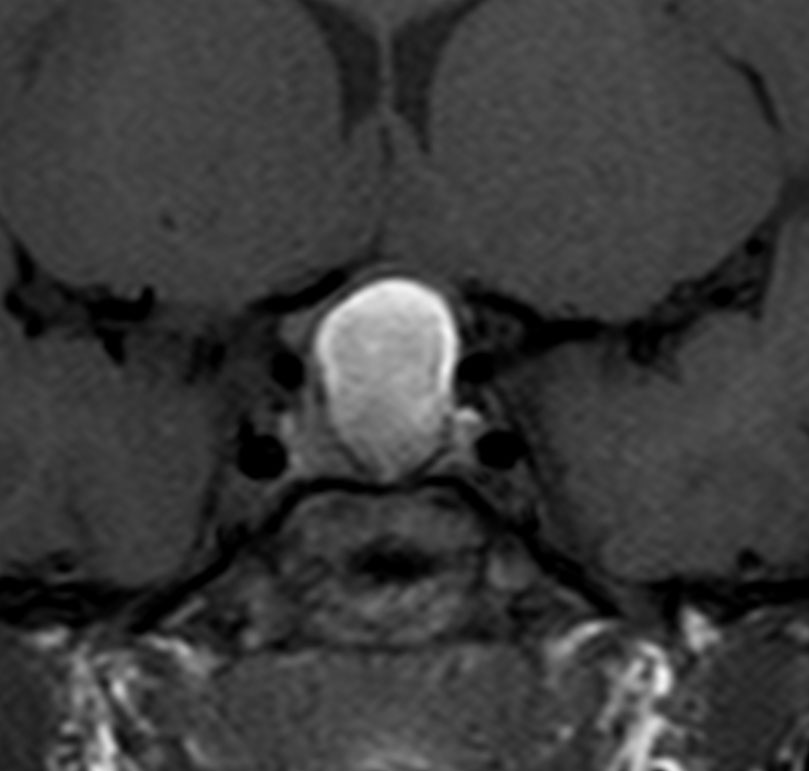

トルコ鞍の中から発生する頭蓋咽頭腫は,身長の伸びが悪い(低身長)とかおしっこの量が多くて水をたくさん飲む(尿崩症)とかで発症します。それから視力の障害。たいていの場合は小さい腫瘍が多くて,鼻孔からの経蝶形骨洞手術で摘出できます。のう胞の部分(右のMRIの真っ白な部分)をつぶすだけの手術だと再発しますから,腫瘍を全部取る手術を目指します。そうしないと何度も手術を繰り返すか,放射線治療をすることになってしまいます。目標は下垂体の機能を少しでも残すことですが,下垂体正常組織との剥離が難しいことも多いです。幼児で副鼻腔(蝶形骨洞)の発達がなくても,ドリルで蝶形骨を削ればこの手術は可能です。でもそれができる外科医は少ないかも。この例は黄色肉芽腫との鑑別が難しいものでした。

9歳児の頭蓋咽頭腫です。視力障害が高度なので鼻の孔(経蝶形骨洞手術)から急いで全摘出しました。腫瘍の塊がトルコ鞍の底にありますが,この部分は開頭手術では多少見づらいです。術後に視力は少し良くなりました。1年後のMRI(右側)では下垂体組織は残っていて,前葉ホルモンは正常ですが軽い尿崩症があります。